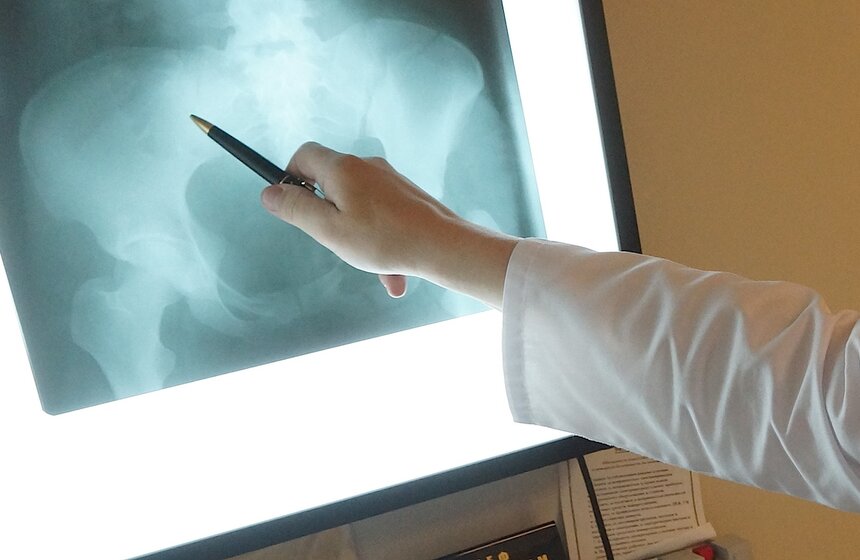

В Боткинской больнице находятся некоторые пострадавшие в трагедии в московском метро. Главврач медучреждения Алексей Шабунин отметил, что пациенты, в зависимости от степени тяжести ранений, будут оставаться в больнице 6-7 дней.

Фото: m24.ru